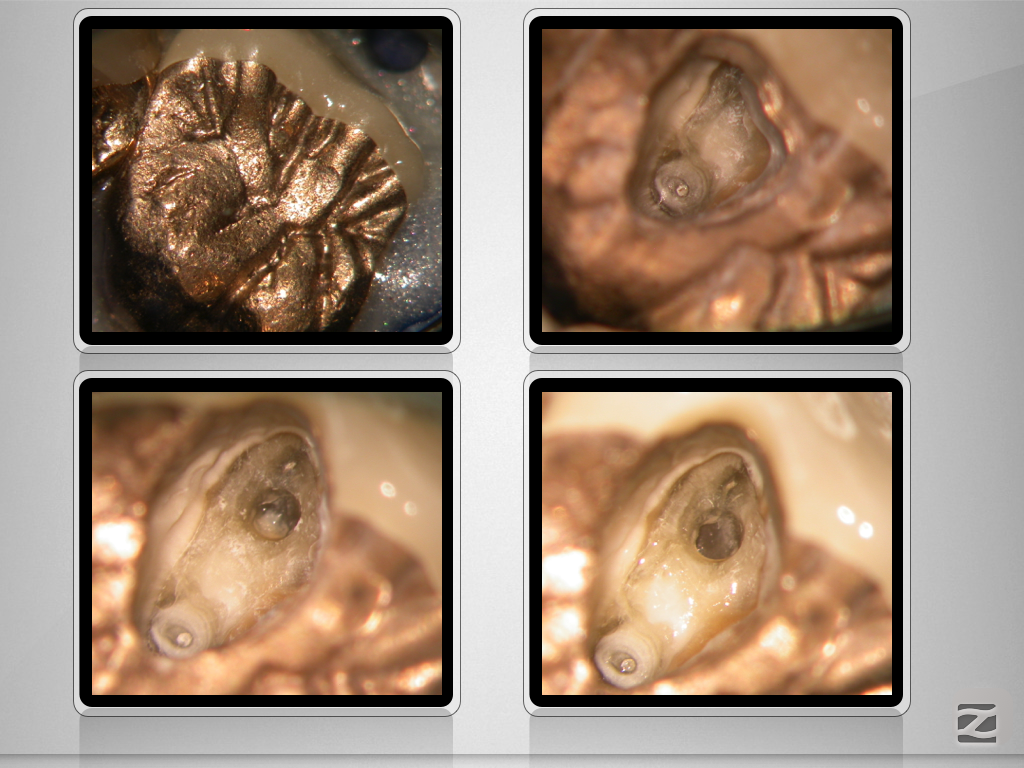

16D.011

Immer schön skeptisch bleiben 4